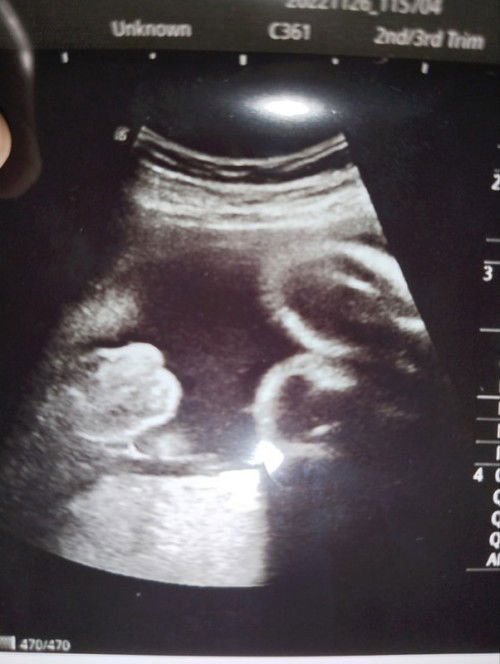

Tak reti sangat tengok ni , doktor kata boy tapi belalai tak nampak sangat . Apa kata mommy semua ? Ada pengalaman scan nampak macam tu tak then keluar apa ? Maaf lah excited sangat . #seriusnanya #ingintahu #pleasehelp #bantusharing